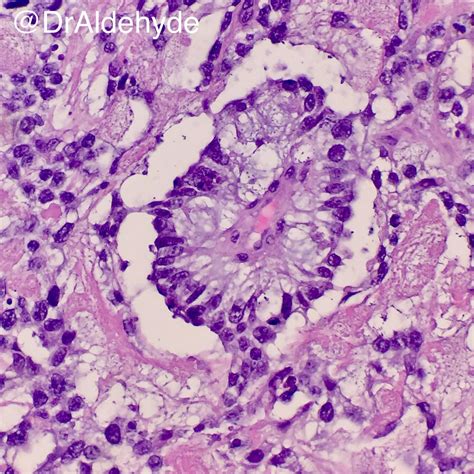

Schiller Duval Bodies are distinctive, glomeruloid structures found within yolk sac tumors. These bodies are named after the pathologists who first described them, Schiller and Duval. They are composed of a central blood vessel surrounded by a layer of tumor cells, which in turn are enclosed by a layer of connective tissue. The unique morphology of Schiller Duval Bodies makes them a reliable marker for the diagnosis of yolk sac tumors.

• Central Blood Vessel: The core of the Schiller Duval Body is a blood vessel, which is often dilated and lined by endothelial cells.

• Surrounding Tumor Cells: The blood vessel is encircled by a layer of tumor cells, which are typically cuboidal or columnar in shape.

• Connective Tissue Layer: The outer layer consists of connective tissue, which provides structural support to the body.

These features collectively contribute to the glomeruloid appearance of Schiller Duval Bodies, which is a hallmark of yolk sac tumors.